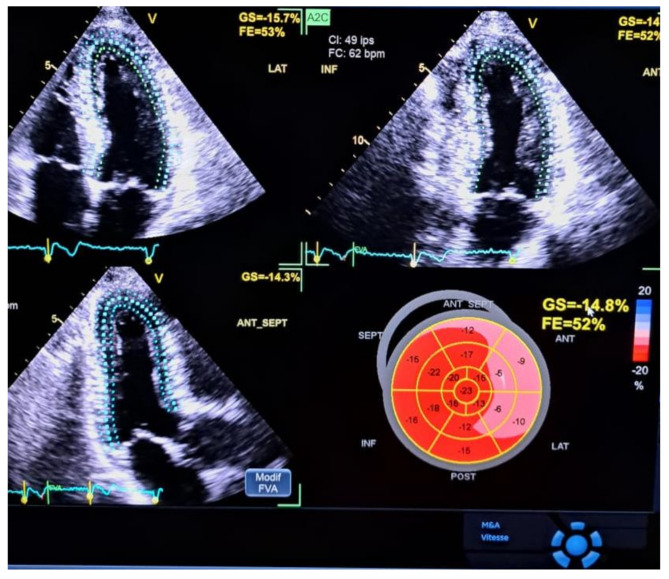

Methods: A prospective study enrolled 52 patients referred for coronary angiography due to highly suspected CCS. Participants were divided into CAD+ (significant stenosis) and CAD- (normal or non-significant stenosis). Transthoracic echocardiography (TTE), exercise EKG, 2D-STE, and coronary angiography were performed. Global longitudinal peak systolic strain (GLS) was calculated using 2D-STE, with a cut-off value of -18% for normal GLS. Reproducibility was assessed with intraclass correlation.

Results: The mean age of participants was 62.5 ± 11.9 years, and 63.5% were male. The CAD + group (51.9%) had significantly higher rates of hypertension, diabetes, dyslipidemia, and typical angina. GLS was significantly lower in the CAD + group (-15.89 ± 2.07%) compared to the CAD- group (-18.99 ± 2.37%, p = 0.0001). The optimal GLS cut-off for detecting significant coronary lesions was - 16.9%, with 74% sensitivity, 76% specificity, and an area under the curve (AUC) of 0.83 (95% CI 0.73-0.94). GLS correlated with the number of diseased vessels (p = 0.0001) but not with lesion complexity (SYNTAX score, p = 0.18). Regional strain was significantly reduced in patients with obstructive lesions in the left anterior descending (LAD) and circumflex arteries (CX), with optimal cut-offs at -19.2% and - 15.8%, respectively. GLS showed excellent inter-operator reproducibility (ICC = 0.94, p < 0.0001).